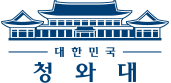

병원비 때문에 파산 위기에 내몰린 벼랑 끝 환자는 무려 16만 명! 또한 저출산, 고령화 사회 등 여러 가지 요인으로 인해 병원비 부담이 늘어나고 있다. 병원비 걱정없이 누구나 행복할 수 있도록 2017년 8월 ‘건강보험 보장성 강화’ 정책 발표! 시행 2년여가 지난 지금 국민의 ‘80%’ 정도가 이 제도에 대해 만족하고 실제 도움이 된다고 말하고 있다. 국민들에게 좀 더 강화 된 건강정보를 제공하는 <메디컬다큐! 건강+ 더하기 행복 시즌2>